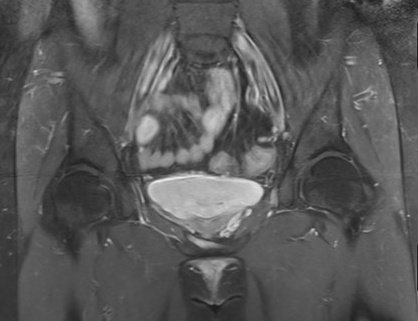

2.增强CT及MRI检查

可显示子宫附件内迂曲、扩张的静脉血管结构。